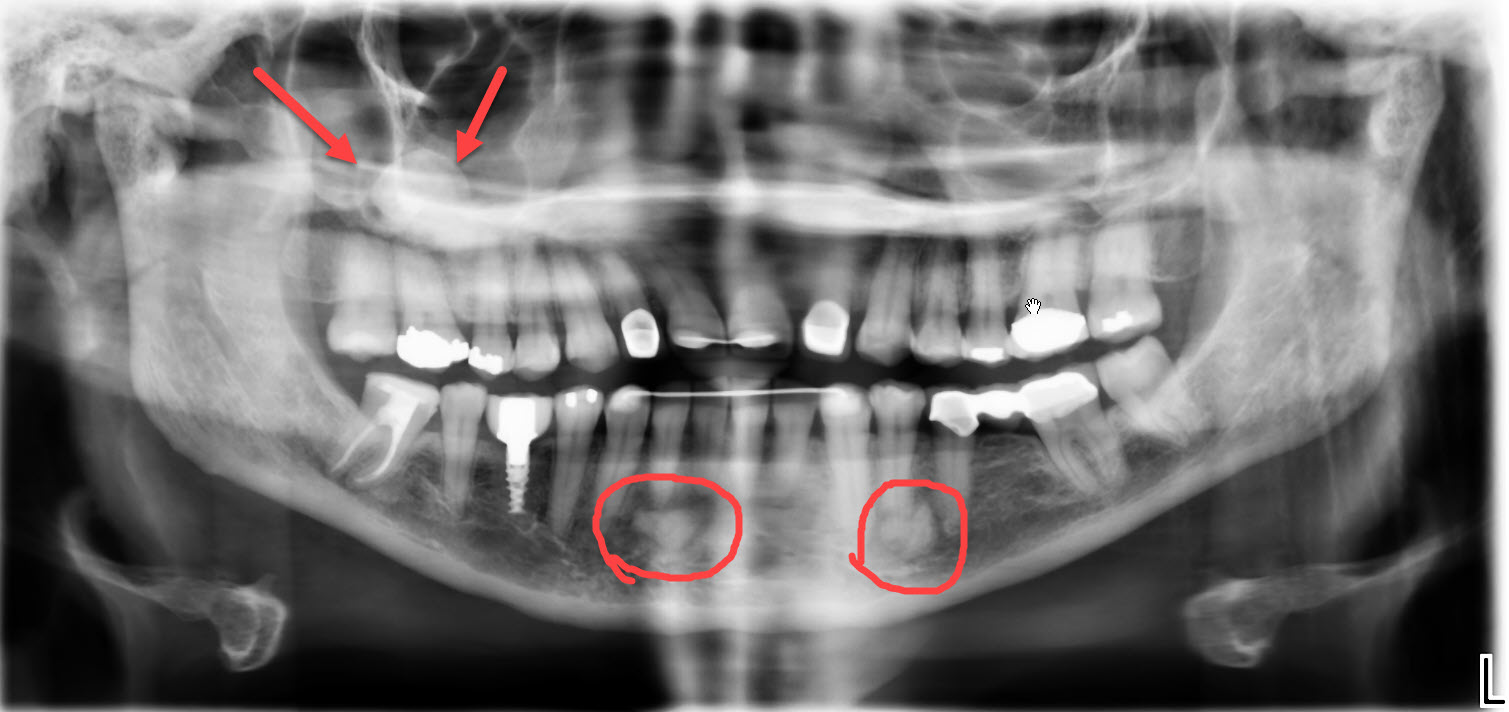

Dental X-rays are more than just tools for diagnosing cavities; they provide a comprehensive view of your oral health status. By allowing dentists to detect problems before they become severe, these images can save patients time, money, and discomfort in the long run. Early detection through modern imaging technology can reveal hidden decay between teeth, bone loss due to gum disease, or even cysts and tumors that are not visible during a standard exam.

- Impacted Teeth - Revealing teeth that are not properly erupting, such as wisdom teeth.

- Tumors - Spotting abnormal growths or cysts within the jawbone.

- Pre-Implant Assessment - Ensuring adequate bone structure for dental implants.

Beyond diagnosis, regular imaging plays a vital role in treatment planning. Whether you're considering braces or implants or undergoing root canal therapy, precise images enable personalized care tailored to your unique anatomy.

Despite the myths surrounding dental x-rays, they play an integral role in preventative dentistry. X-rays allow dentists to detect issues that are not visible during a standard oral exam. This includes early signs of decay between teeth, problems below the gum line, and changes in bone density that could indicate periodontal disease. By identifying these problems early, fundamental dental treatments can be administered promptly, saving patients from more extensive and costly procedures down the line.

Dental x-rays also serve as a critical tool in planning complex dental treatments such as orthodontics, implants, and extractions. The detailed imagery helps create precise treatment plans tailored to each patient's unique anatomy. To explore how modern technology is shaping these plans, visit our page on digital dentistry benefits.